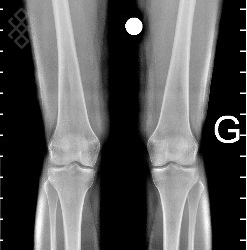

TéléRadiographie des Membres Inférieurs

Vous serez installés en position verticale avec les pieds joints.